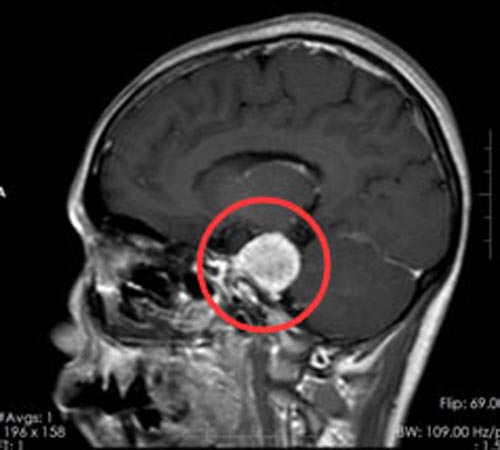

45岁的陈阿姨一直以来身体都是健健康康的,可半个月前,她突然出现左侧发作性面部疼痛,陈阿姨描述:像触电一样的疼痛,日常生活中的洗脸、吃饭等都会引起,偶尔还会感觉头痛头晕。在当地医院头颅CT检查,结果提示:左侧示一团块状占位性病变,呈稍长异常信号影,大小约为3.0cm×2.0cm×2.8cm,考虑左侧桥小脑角占位,为进一步的检查和治疗,陈阿姨和家人一起来到广东三九脑科医院。

入住综合神经外科后,医生给陈阿姨做了更详细的检查,结果诊断为:1.左侧小脑幕下占位,考虑脑膜瘤;2.继发性左侧三叉神经痛。和陈阿姨及家属详细地介绍了手术方案,由鲁明副院长主刀,在全麻下行“左侧小脑幕下脑膜瘤切除术”。术中见颅窝靠近右侧岩斜区黄白色肿物,质硬,血供一般,筋膜粘连紧密,边界较清,用吸引器分块切除黄白色肿瘤,肿瘤组织根部位于右侧岩斜区内侧面,对桥脑有压迫,显微镜下将肿瘤全切,神经、血管保护良好,手术过程非常顺利。

▲手术前